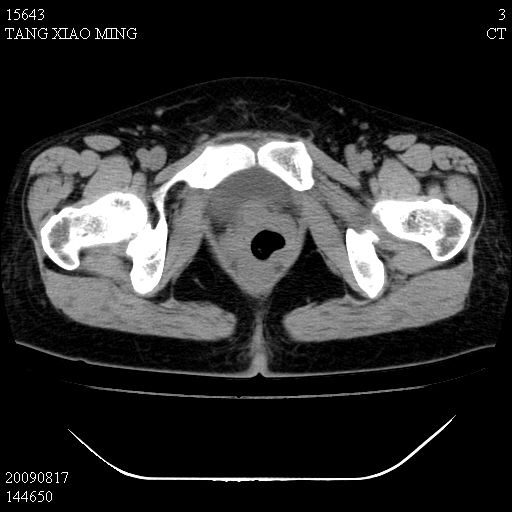

标题: CT21692:盆腔病变

女,33岁,右下腹痛2年余,既往宫外孕病史,如在我院手术,结果下周公布,

可能的诊断。1子宫内膜异位【子宫腺肌症并右卵巢巧克力囊肿】;2 右卵巢囊腺瘤。子宫肌瘤

1)考虑卵巢巧克力囊肿,不排除卵巢囊腺瘤。2)子宫肌瘤可能。

卵巢囊腺瘤,子宫肌瘤,直肠壁厚,不除外占位.